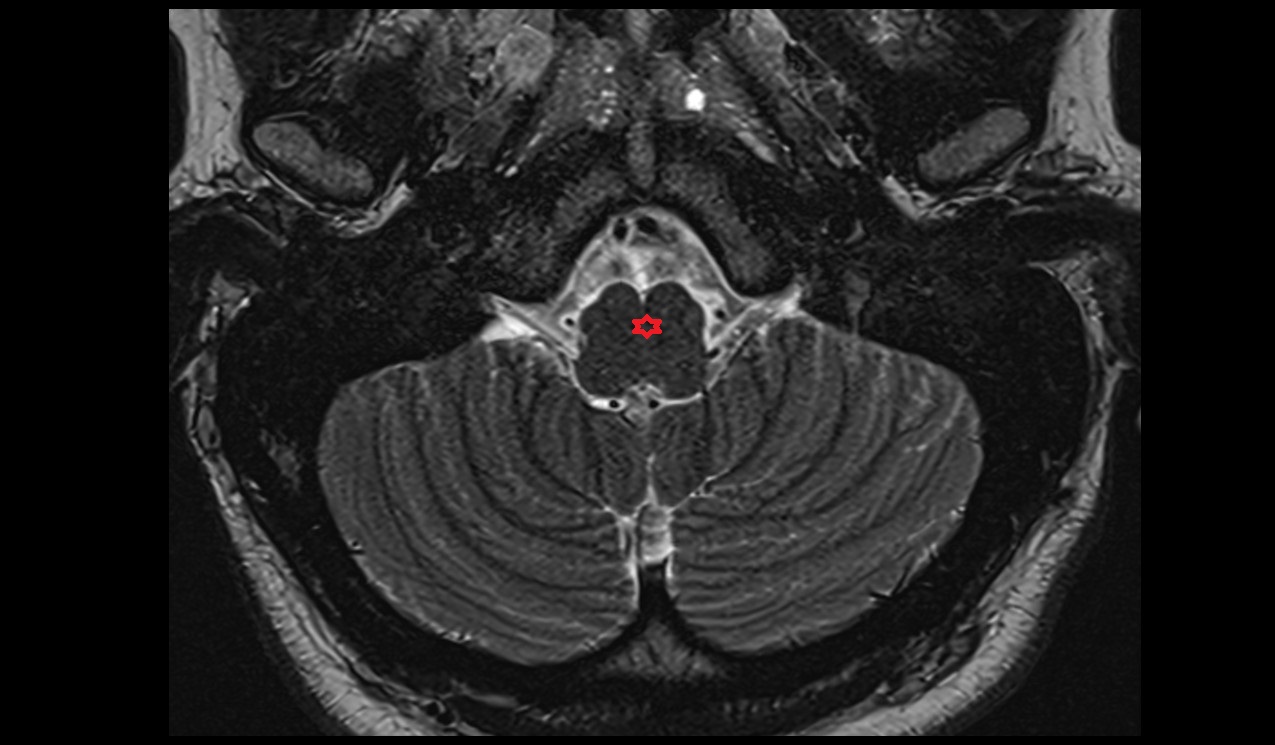

- Cerebellum